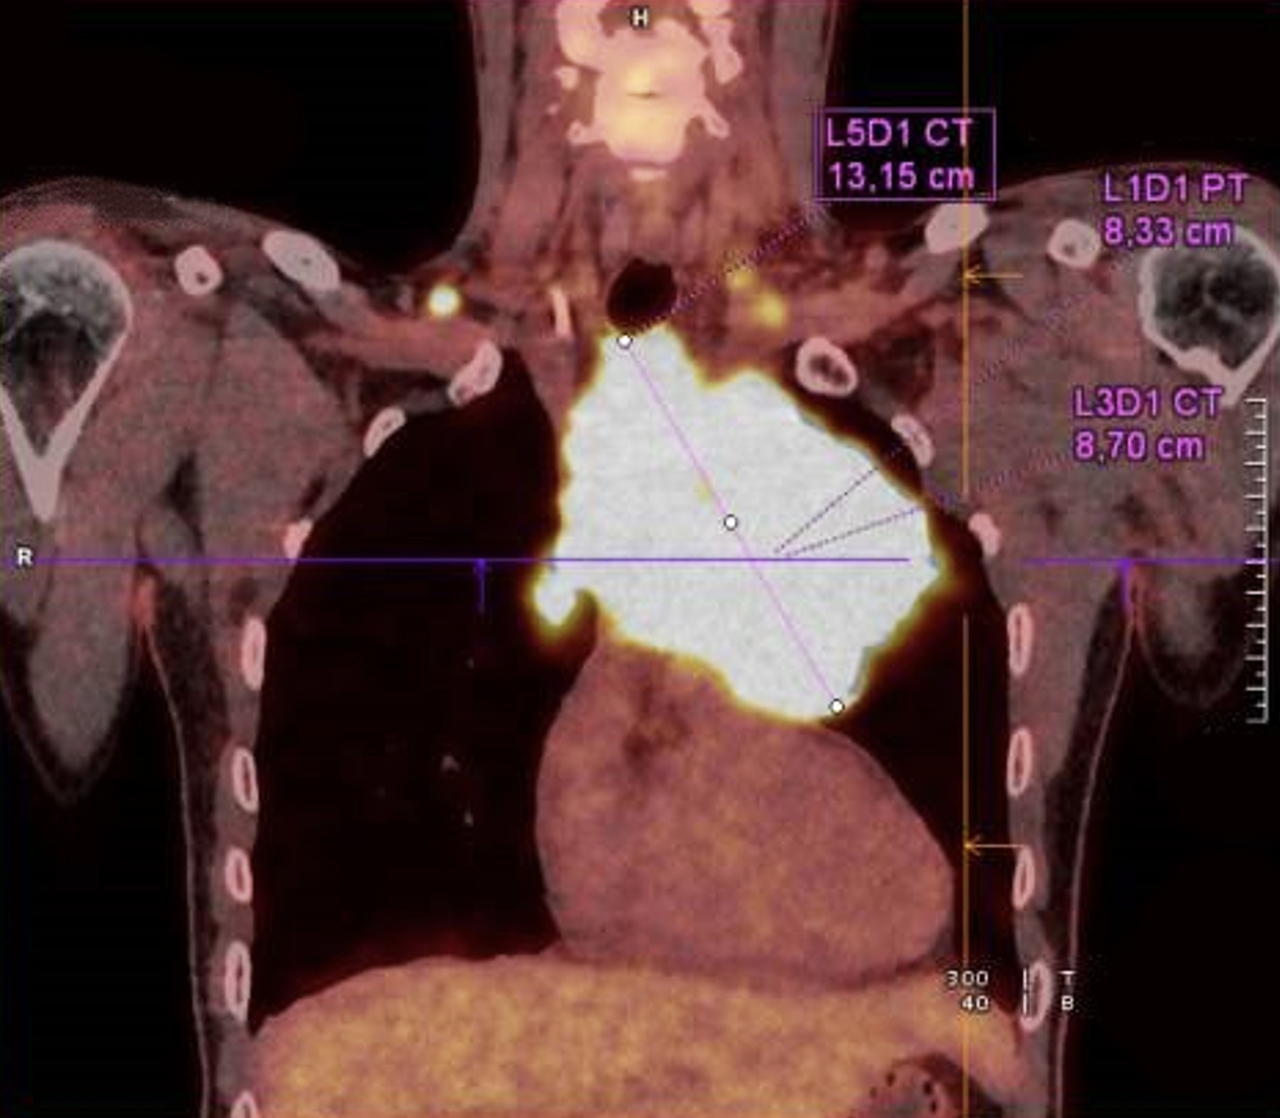

Devant des D Dimères élevés, un angioscanner est réalisé, complété par un TEP scanner au 18 FDG.

Le lymphome B médiastinal primitif (LBPM) est un lymphome à grandes cellules siégeant dans le médiastin antérieur. La lésion est le plus souvent volumineuse, elle peut envahir les organes de voisinage et entrainer un syndrome cave supérieur.